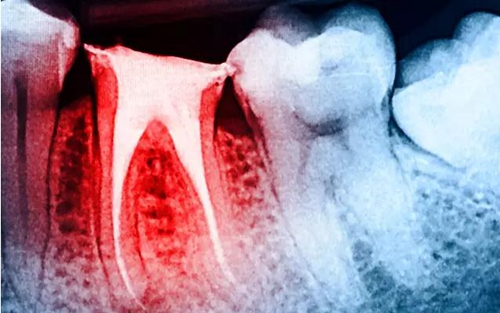

大量研究表明:與活髓牙相比,根管治療后牙體組織的強(qiáng)度、韌性以及硬度等力學(xué)性能均無(wú)明顯改變,牙髓活力對(duì)牙齒的生物力學(xué)性能的影響十分有限;而齲損組織、舊充填物和后續(xù)的治療修復(fù)過(guò)程造成的冠根部牙體組織的喪失才是引起牙齒抗折強(qiáng)度降低的主要原因。牙體強(qiáng)度與剩余牙體組織的量密切相關(guān),牙體組織缺損愈多,抗折力降低愈明顯。